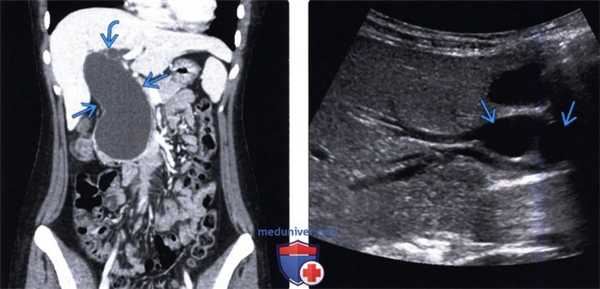

(Левый) У пациента с кистой холедоха I типа на продольном трансабдоминальном УЗ срезе определяется выраженное веретеновидное расширение внепеченочного желчного протока.

(Правый) У этого же пациента на поперечном УЗ срезе в черно-белом режиме визуализируется значительно расширенный общий проток, имеющий вид кисты в воротах печени. Желчный пузырь (GB) лежит кпереди отдельно от кисты холедоха (I тип).

(Левый) При КТ с контрастным усилением на корональном срезе у этого же пациента определяется значительное веретеновидное расширение общего протока, сообщающееся с внутрипеченочными протоками, что соответствует кисте холедоха I типа.

(Правый) На продольном ко сом УЗ срезе ворот печени в черно-белом режиме определяется многокамерный общий проток с двумя отдельными камерами, что соответствует кисте холедоха IVb типа.